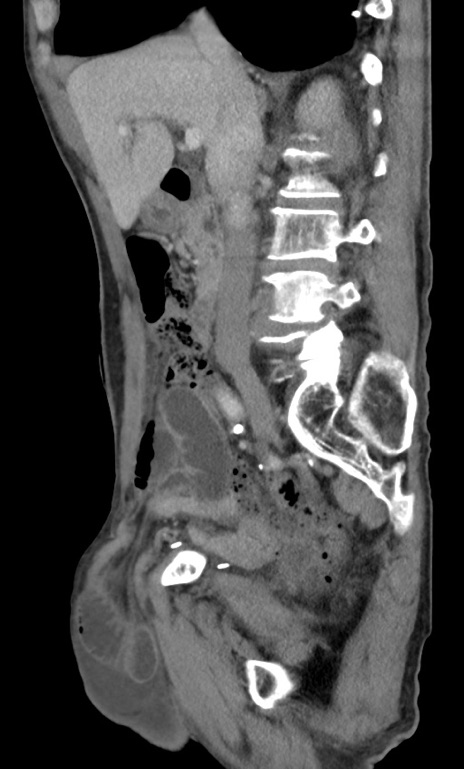

症例3(矢状断像)

【症例】 70歳代男性

【主訴】右鼠径部腫瘤、疼痛

【現病歴】本日朝より上記主訴あり、受診。

【既往歴】膀胱癌にて膀胱全摘、両側尿管皮膚瘻

【データ】WBC 5600、CRP 0.56